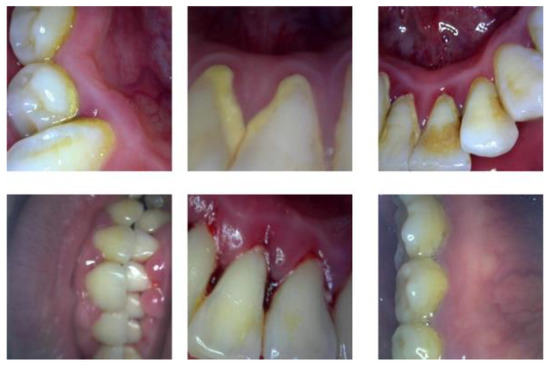

An intraoral camera was used to collect images of dental calculus, gingivitis, tartar, and worn surfaces. Two hundred images of dental lesions were obtained by shooting from three angles: the exterior, interior, and top views. The number of occurrences of various lesions in the collected images are shown in Table 1.

To expand the difference between the samples and ensure the generalization ability of the later model training, randomly crop the collected dental lesion pictures and restore the original size and flip it over, then adjust the contrast, brightness, saturation, etc. Then, the original tooth lesion image is scaled to 512 × 512 pixels according to the principle of proportional invariance, the distorted image is removed by manual screening, and 400 dental lesion images are selected as the original dataset. Figure 7 shows that dataset example and Figure 8 shows that the number of various lesions before and after data augmentation. Finally, the Label Me labeling tool was used to imitate the PASCAL VOC2012 dataset format to manually label the four categories of calculus, gingivitis, tartar, and wear surface in the lesion image and the dataset was divided into a training set, validation set, and test set at a ratio of 7:2:1.

Figure 7. Example of combined dataset.